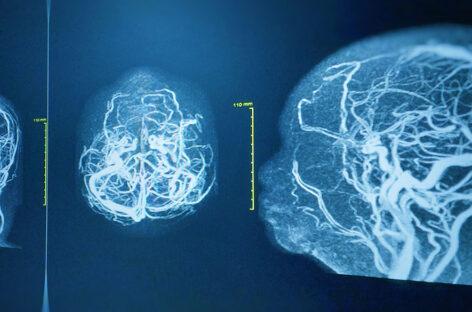

A brain angiogram is a specialised imaging test used to evaluate blood vessels in the brain. It is recommended for children with suspected vascular abnormalities such as aneurysms, arteriovenous malformations, stroke, or unexplained seizures.

The procedure involves inserting a thin catheter through a blood vessel, usually in the groin, and guiding it to the brain. A contrast dye is injected, and detailed images are captured to study blood flow and vessel structure.